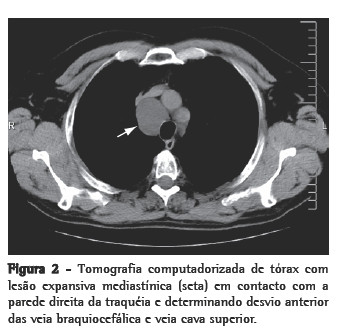

O doente apresentava-se assintomático e sem alterações de relevo ao exame físico-auscultação pulmonar e saturação periférica de oxigênio normais e sem turgescência venosa jugular a 45°. Não apresentava alterações no estudo da função pulmonar, e o exame eletrocardiográfico era normal. Foi efetuada tomografia computadorizada torácica, que revelou uma lesão tumoral mediastínica, em localização paratraqueal direita, com 4,5 cm de diâmetro, em contato com a parede direita da traquéia e determinando desvio anterior das veias braquiocefálica e cava superior. A massa apresentava contornos regulares, baixa densidade espontânea, homogênea e sem realce após administração de contraste (Figura 2).

O diagnóstico provável é feito pela detecção de uma lesão cística na radiografia ou tomografia computadorizada de tórax.(5) Na radiografia, os linfangiomas do mediastino observam-se como massas arredondadas, bem circunscritas e de densidade homogênea,(5) sendo que a tomografia computadorizada de tórax nos permite evidenciar o envolvimento ou desvio de estruturas naturais, ausência de calcificação e várias áreas de atenuação dentro da lesão.(2)